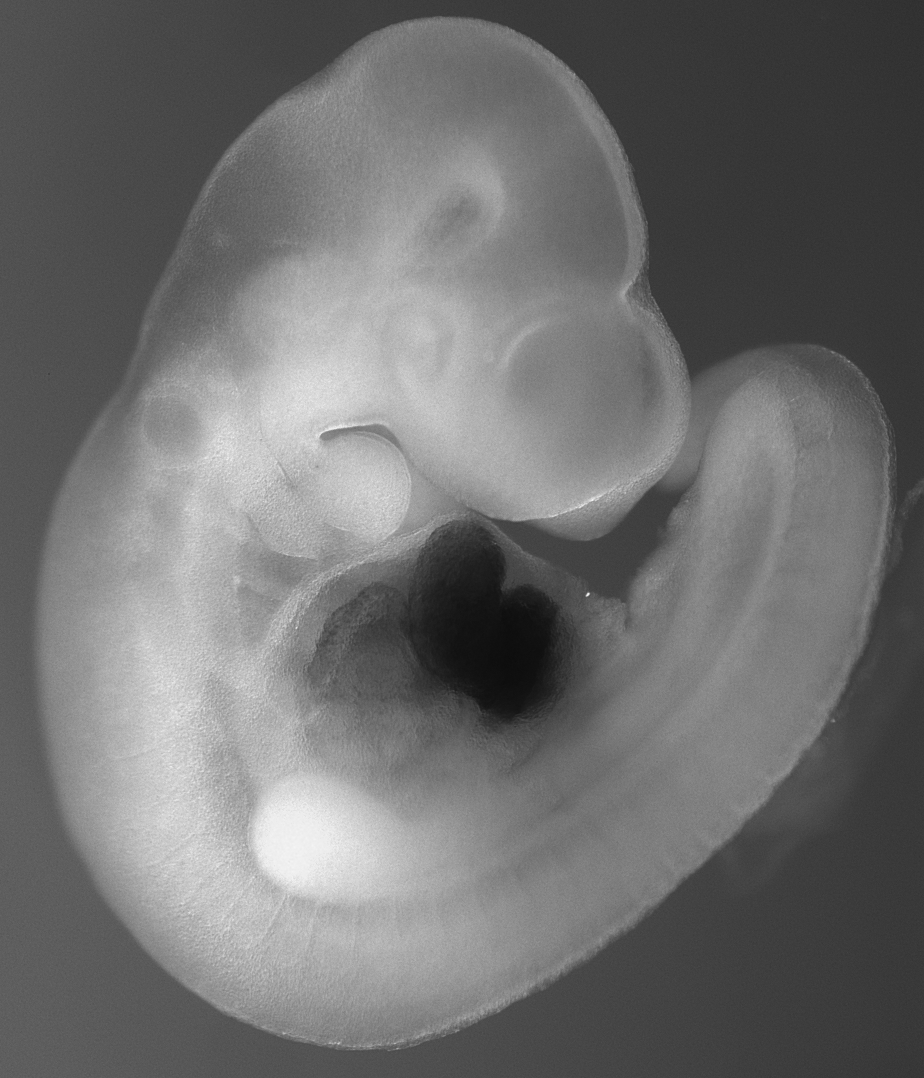

One in 1000 infants exhibits cardiac defects due to genetic alterations during development. We are dedicated to analyze the contribution of long non-protein coding RNAs (lncRNAs) in this process by combining an fast in vivo approach and state of the art genome editing tools.